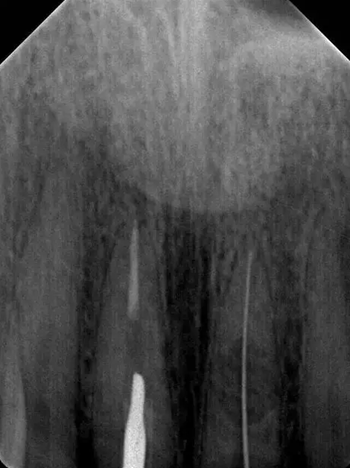

診斷:左上中切牙牙根內吸收。治療計劃:左上中切牙根管治療,全冠修復。 治療過程:患者知情同意。使用含1/100,000腎上腺素的4%鹽酸阿替卡因(碧蘭麻,艾龍)局部浸潤麻醉,橡皮障隔濕。去腐未盡露髓,露髓孔出血多。開髓,使用10#不銹鋼K銼(MANI,日本)探查根管,根管中段有鈣化物阻擋,不能達到牙根全長(圖3A)。在顯微鏡下(Leica M400E,萊卡, 德國) 使用超聲尖(E1根管治療超聲尖,啄木鳥公司,中國)通開,采用根管長度測量儀(Root ZX, Morita公司,日本)加診斷絲片法(圖1B)測量根管長22 mm。使用控制扭矩馬達(X-smart,登士柏)和鎳鈦旋轉器械(Hero 642, Micromega)根管預備,根管預備過程中使用5.25%次氯酸鈉溶液沖洗。 根備完成后使用超聲蕩洗根管,5.25%次氯酸鈉溶液3 分鐘, 17% EDTA溶液1分鐘。干燥根管,使用螺旋充填器根管內封氫氧化鈣糊,氧化鋅丁香油水門汀暫封。1周后患者復診,患者述無術后不適,檢查暫封完好,無叩痛,不松,牙齦無紅腫瘺管。使用橡皮障隔濕,去除暫封物,超聲蕩洗根管,5.25%次氯酸鈉溶液3 分鐘, 17% EDTA溶液1分鐘。干燥根管,牙膠尖(達雅鼎,中國)和必蘭根充糊劑(Cortisomol, 艾龍公司,法國)熱垂直加壓法根管充填。術后片顯示根充恰填,可見牙膠/糊劑被壓入鈣化物周圍和內部縫隙內

1月后復查無不適,行全瓷冠修復。8月2周后復查,患者無不適主訴,牙冠美觀,邊緣完好,患牙無叩痛,不松動,牙齦無紅腫瘺管, X線片示根周膜連續,根尖周未見異常。建議患者避免用前牙撕咬食物,定期復查。 討論: 臨床上,由于牙根內吸收和牙根外吸收的治療方法和預后不同,常需要對兩者進行鑒別診斷。過去通常采用偏移投照的方法鑒別兩者。在偏移投照片上,外吸收病損和根管輪廓相對位置較正位片會發生變化,而內吸收病損則不會[12]。